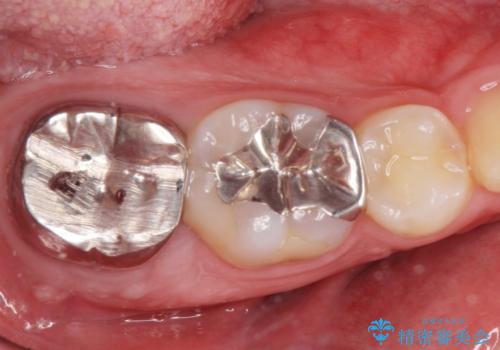

[銀歯の下が虫歯に] ジルコニアクラウンで修復

- 銀歯の下が虫歯になっていたので拡大鏡下で虫歯を取り除き、ジルコニアクラウンで治療を行いました。

- ジルコニアクラウンスタンダード・仮歯 12.1万円費用は治療当時の料金となります